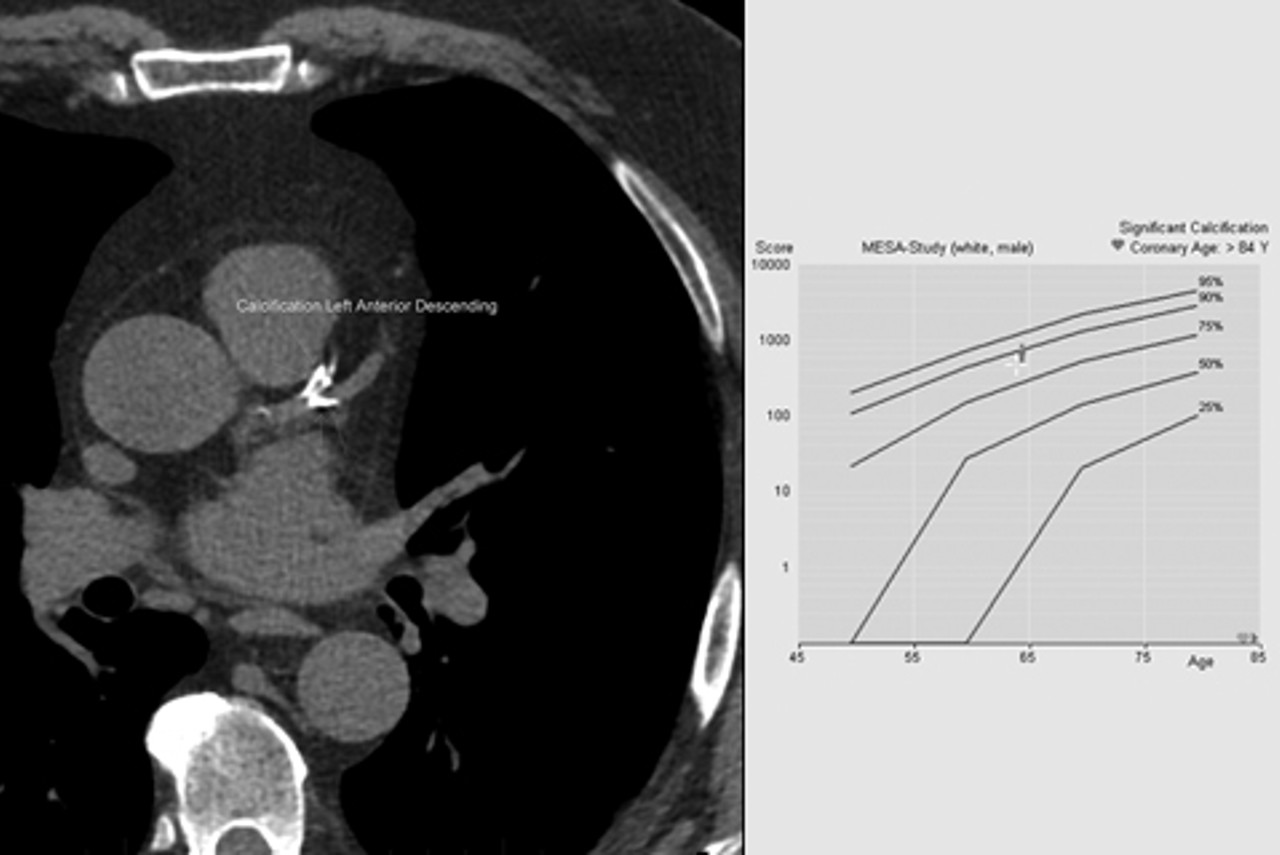

The scan is used to estimate the amount of calcification in your coronary (heart) arteries and return this as a calcium score. Based on this, your future risk of a significant event, such as a heart attack, can be determined. A comparison will also be made with others of the same age and gender found in international studies to determine whether you have more, or less calcification than expected.

Based on the scan results and other factors, your doctor will decide on the need for preventative treatment or further necessary investigations.